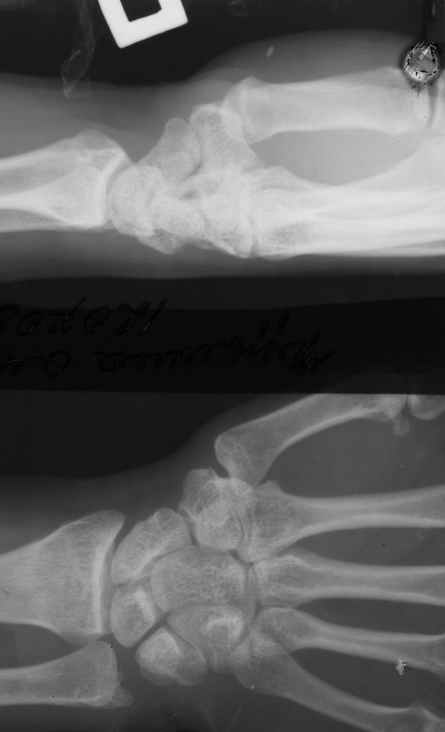

Диагноз: Стойкая Смешанная дермотеногенная контрактура 3,4 пальца правой кисти.